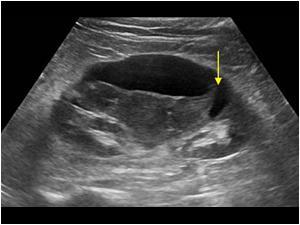

Pancreatic Psydocyst

Spherical fluid collection of pancreatic enzymes that arise from inflamatory, necrotic and hemorrhage processes of the pancrreas

persistently elevated amylase and lipase

Pancreatic Psydocyst

Spherical fluid collection of pancreatic enzymes that arise from inflamatory, necrotic and hemorrhage processes of the pancrreas

persistently elevated amylase and lipase

Pancreatic Psydocyst

Spherical fluid collection of pancreatic enzymes that arise from inflamatory, necrotic and hemorrhage processes of the pancrreas